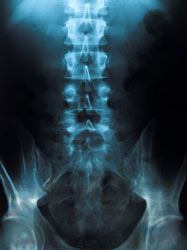

La columna de la degeneración de la espina dorsal

Los dolores de espalda causan pérdida de calidad de vida a la persona que los padece, por no hablar de la grave carga financiera que representan para los servicios sanitarios. Un proyecto europeo ha investigado los motivos que subyacen a la senescencia en los discos intervertebrales como una clave potencial para terapias efectivas.

La espina dorsal humana es una estructura compleja y dinámica. Puede soportar el peso de la cabeza y aun así permite la flexibilidad suficiente para sentarse, bailar y levantar pesos. Todo esto, claro está, hasta que se degenera. Esto puede ocurrir a una edad temprana y entonces puede provocar hernias discales, dolores y discapacidad crónica, en particular en las personas mayores. Los miembros del proyecto EURODISC investigaron las relaciones entre el envejecimiento, el entorno y los factores genéticos que contribuyen a esta desafortunada espiral de declive. La senescencia celular es un fenómeno que se ha vinculado a enfermedades degenerativas en otros tejidos. Esto se produce cuando una célula no puede dividirse para generar nuevas células hermanas. Un equipo de científicos del hospital Robert Jones y Agnes Hunt en Shropshire han investigado si este proceso, característico del envejecimiento, se produce en diferentes tejidos del disco espinal. El grado de senescencia fue evaluado mediante dos criterios. Primero, un biomarcador asociado con la senescencia en tejidos y, segundo, el número de células en un agrupamiento, que aumenta directamente con el paso de la edad. Los investigadores observaron que el grado de senescencia variaba dependiendo del tipo de degeneración. Por ejemplo, los discos herniados mostraban el mayor porcentaje de células envejecidas en comparación con otras enfermedades degenerativas. Asimismo, el tipo de tejido dentro del disco era importante. Cada disco está formado por una parte central blanda, el núcleo pulposo rodeado por anillos de tejido conectivo. La senescencia se asociaba más comúnmente con el núcleo blando, donde se vio que se producían los agrupamientos celulares. Estos resultados tienen importantes implicaciones para el desarrollo de dolencias de espalda y su tratamiento. Primero, la ingeniería de tejidos es una posibilidad real para la terapia de discos, por la que se sustituye el tejido. Parece que entonces las células del tejido degenerativo no serían aptas para su uso. Segundo, la presencia de células senescentes se asocia, en general, con un comportamiento anormal de los tejidos y, por tanto, puede resultar ser la causa principal de la degeneración espinal. Estos resultados se han publicado en la página Web del proyecto: http://www.physiol.ox.ac.uk/EURODISC/(se abrirá en una nueva ventana) Los resultados del proyecto están bien explicados tanto para el público como para los investigadores interesados en el campo. También se han difundido en encuentros de expertos, revistas y conferencias.